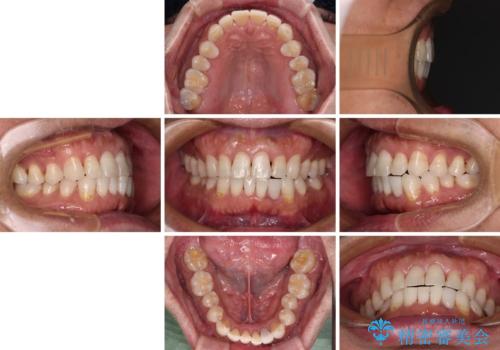

内側にある歯が干渉する 上顎前歯の部分矯正

- 上顎の前歯が内側にあり、下顎のセラミッククラウンと干渉することが気になるとのことで来院された患者様です。

上顎前歯にワイヤー装置を装着し、セラミッククラウンとは干渉しないようにしながら歯列を整えることとしました。

セラミッククラウンとの干渉はすぐに改善され、歯列も整いましたが、一方で、前歯で食事が噛みにくくなり、1年近い治療期間となりました。